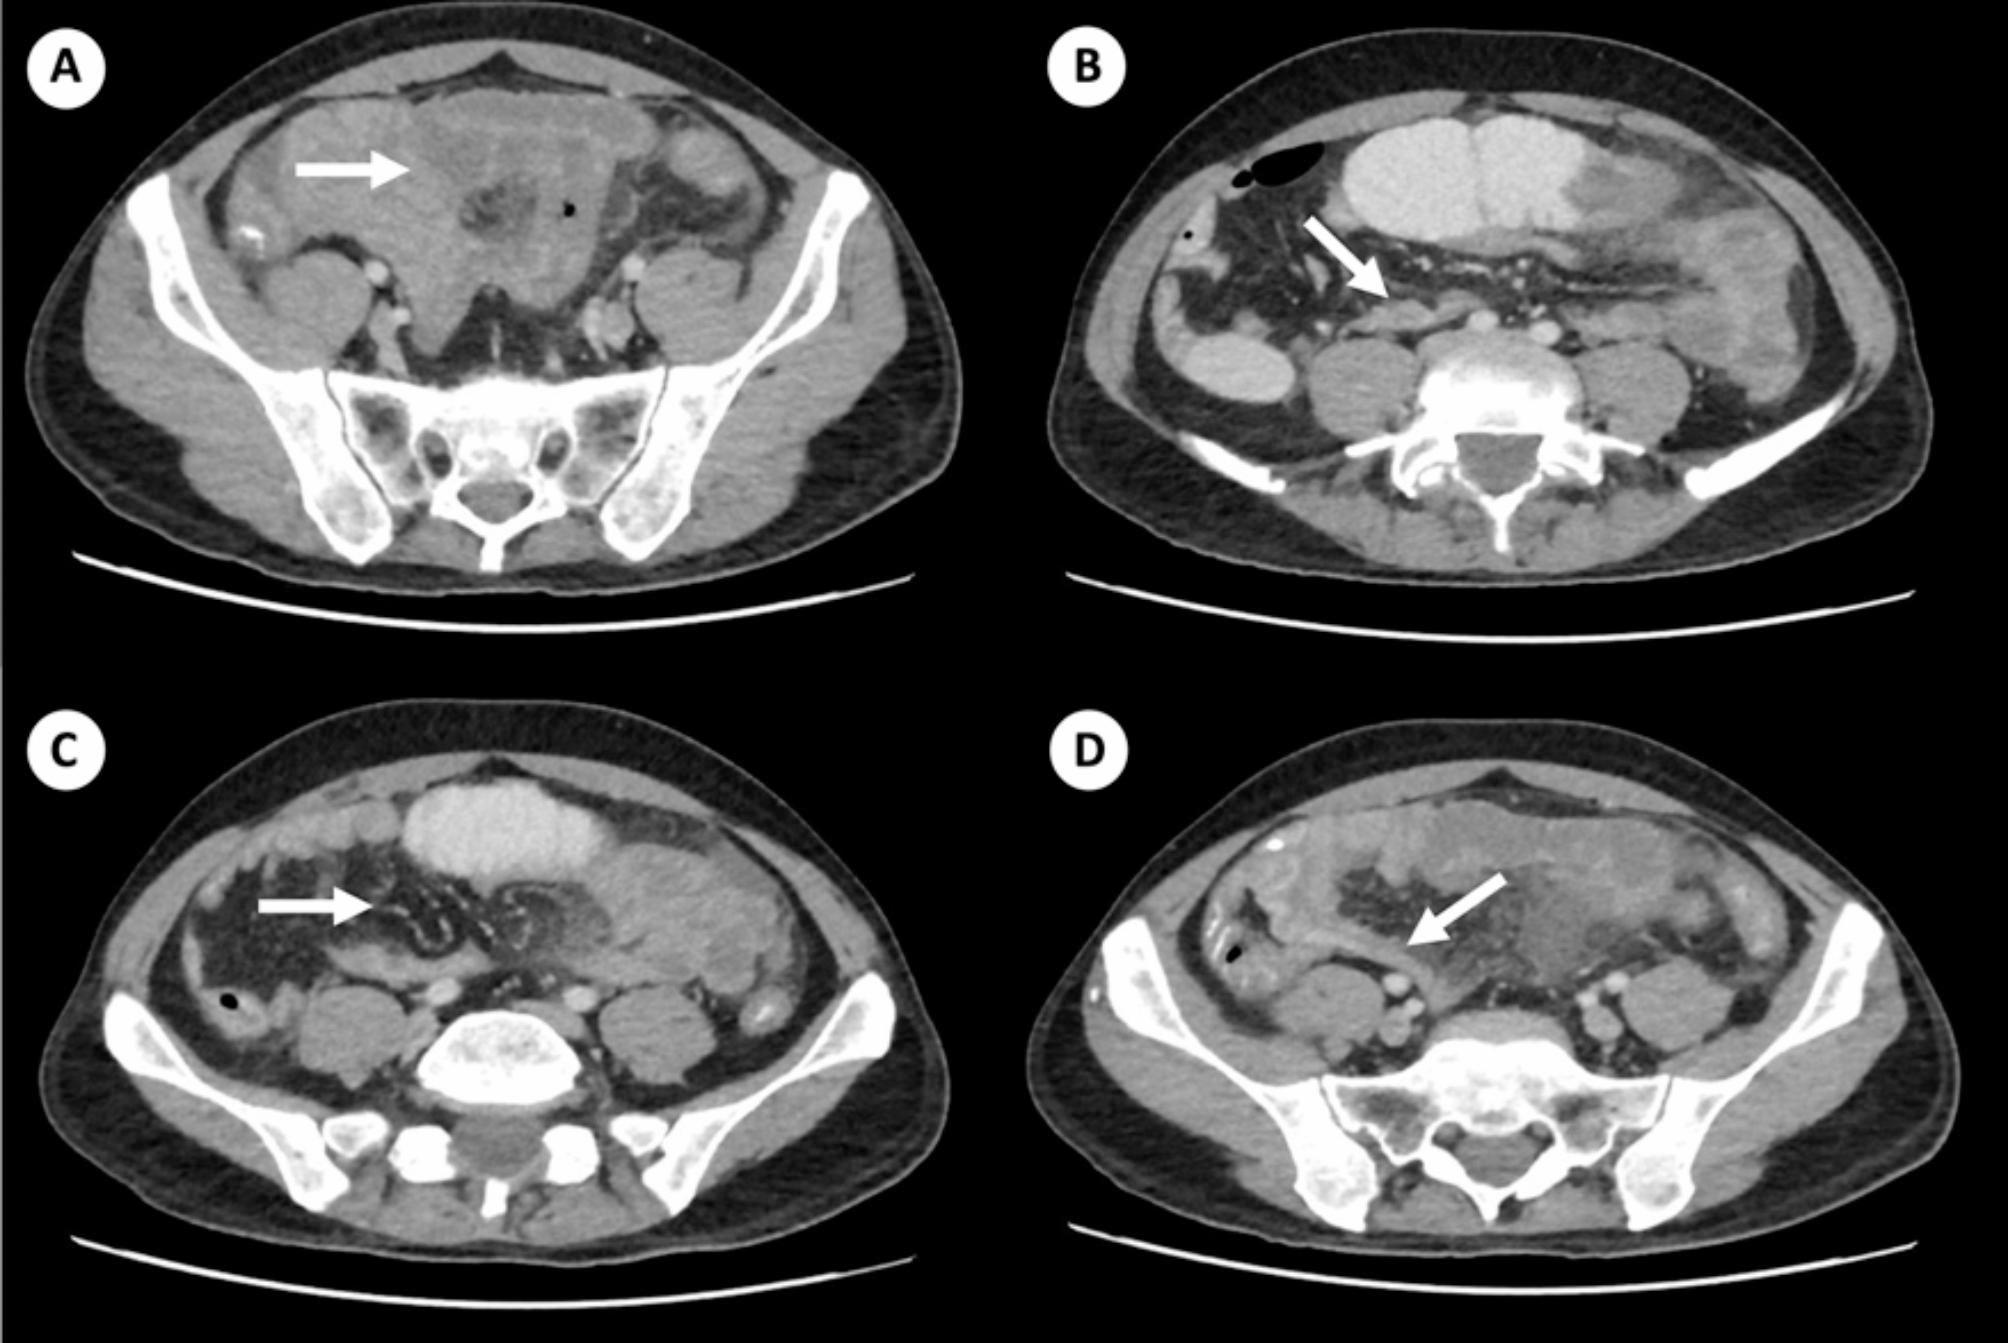

Case presentation: Here we present the case of a 48-year-old male patient with a 9-year history of human immunodeficiency virus (HIV) infection who was hospitalized in the context of febrile neutropenia and whose acute respiratory infection was documented; therefore, antibiotic treatment was initiated. However, due to persistent febrile peaks and peripheral blood showing documentation of multilineage cytopenias, a bone marrow biopsy was performed, compatible with presenting features of marrow myelodysplasia. During hospitalization, the patient presented left flank abdominal pain, and an abdominal computed tomography (CT) scan revealed signs of intussusception of a small bowel loop at the distal jejunum level, leading to intestinal obstruction with ischemic progression, requiring ileectomy (60 cm). Histopathological analysis of the resected intestine revealed severe transmural ischemic changes associated with venous thrombosis due to fungal structures, with histochemical studies demonstrating the presence of zygomycete (Mucor) fungal structures, leading to the initiation of treatment with amphotericin B. However, despite treatment, the patient experienced progressive clinical deterioration with persistent fever and ventilatory failure, with follow-up tests showing absolute neutropenia and blood cultures positive for yeast, leading to death 52 days after admission.